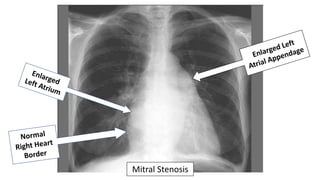

Valvular Heart Disease

Which cardiac chamber is enlarged in patients with significant chronic

mitral stenosis?

• Right atrium

• Right ventricle

• Left atrium

• Left ventricle

Mitral Stenosis

• Left atrial enlargement from mitral stenosis